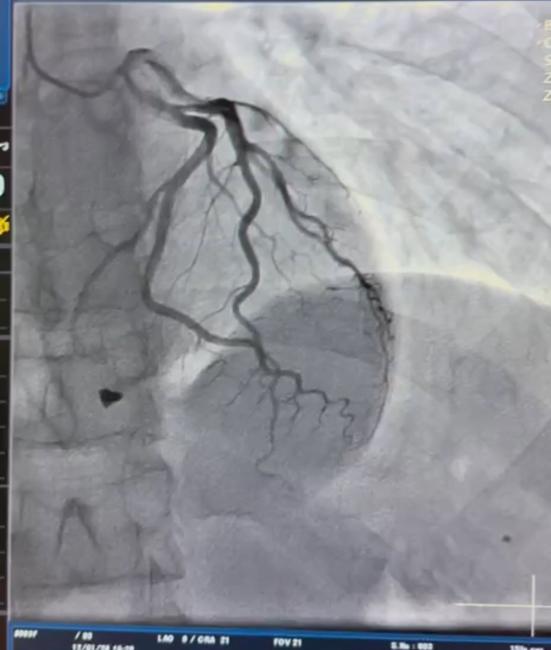

У Вінницькій обласній клінічній лікарні ім. М. І. Пирогова кардіохірурги врятували життя молодого чоловіка з проникаючим пораненням серця. Під час обстеження з’ясувалося, що металевий уламок «застряг» у зоні клапанного апарату та пошкодив папілярний м’яз тристулкового клапана — це серйозна загроза повноцінній роботі серця.

Кардіохірургічна команда провела видалення осколка та пластику тристулкового клапана, відновивши його функцію і забезпечивши стабільну роботу серця. Лікарі підкреслюють, що подібні втручання належать до найскладніших у сучасній кардіохірургії:

- потрібна точна передопераційна візуалізація,